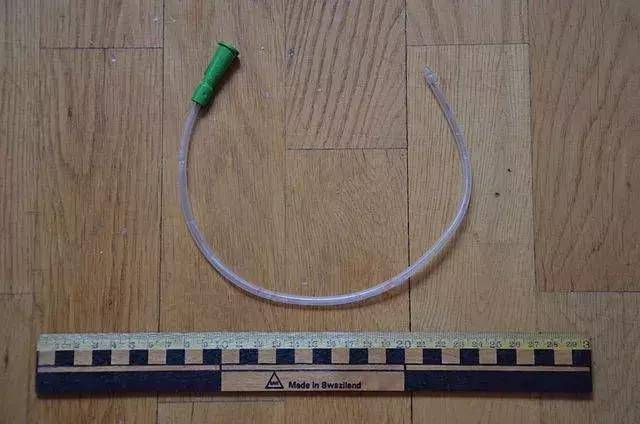

一開始,格爾達在聽到福斯曼說要將軟導管塞進心臟,也莫名恐慌。

之後,他便拿起一根潤滑過的導尿管,緩慢地插入到自己靜脈大約30釐米處。

導尿管

通過鏡子裡螢光屏的指引,福斯曼再一步一步地將導管深入自己的身體裡。

終於,當導管深入福斯曼體內65釐米時,導管進入了福斯曼的右心房。